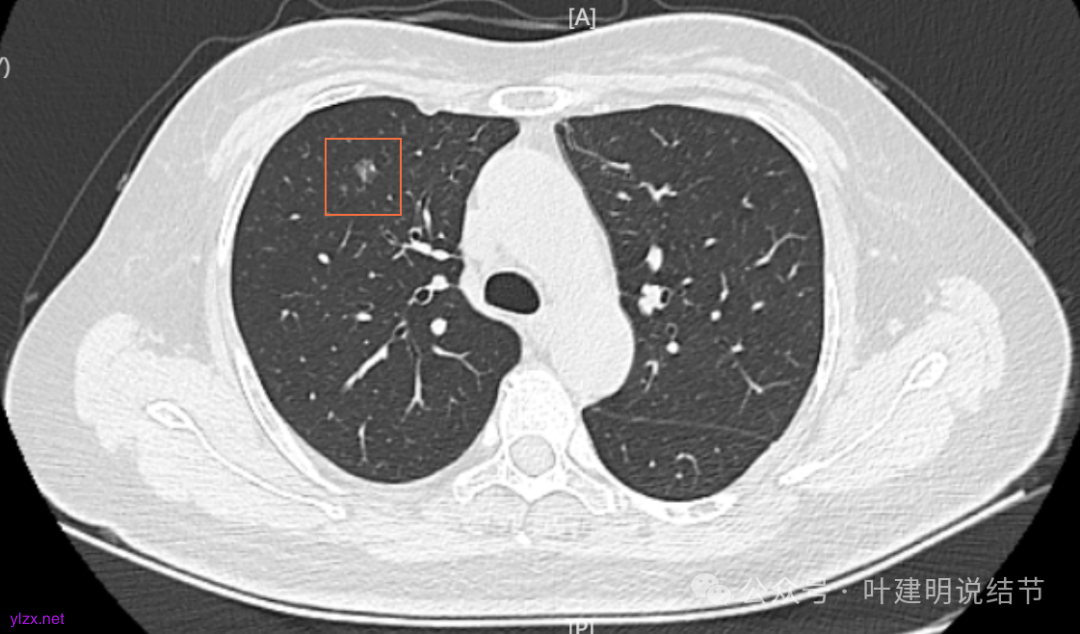

1.2021年12月因感冒咳嗽做了胸部CT,显示多发结节。有大的0.7*0.5cm。

2.2022年5月2日复查增强CT,显示肺结节0.7*0.6cm

4.2022年7月31日做了ct复查,报告显示结节增大,0.8*0.7cm。

病灶7:右下叶胸膜下淡而微小的磨玻璃结节,考虑肺泡上皮增生可能性大。